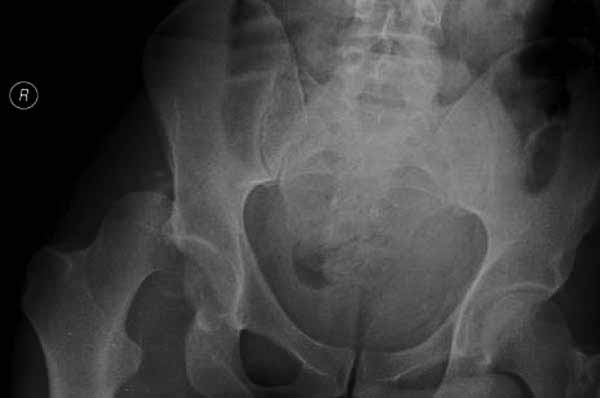

Представлены несколько вариантов фиксации: первый случай перелом головки с задним краем, операция из заднего доступа Кохер, а второй случай изолированный перелом головки - из трохантерного доступа.

Имя     : 2-6 Fem head  fx-dislocation.jpg

Тип     : image/jpg

Размер  : 18301 байтов

Описание: отсутствует

Url     : http://weborto.net:8080/pipermail/ortho/attachments/20111231/d311d17a/attachment-0012.jpg